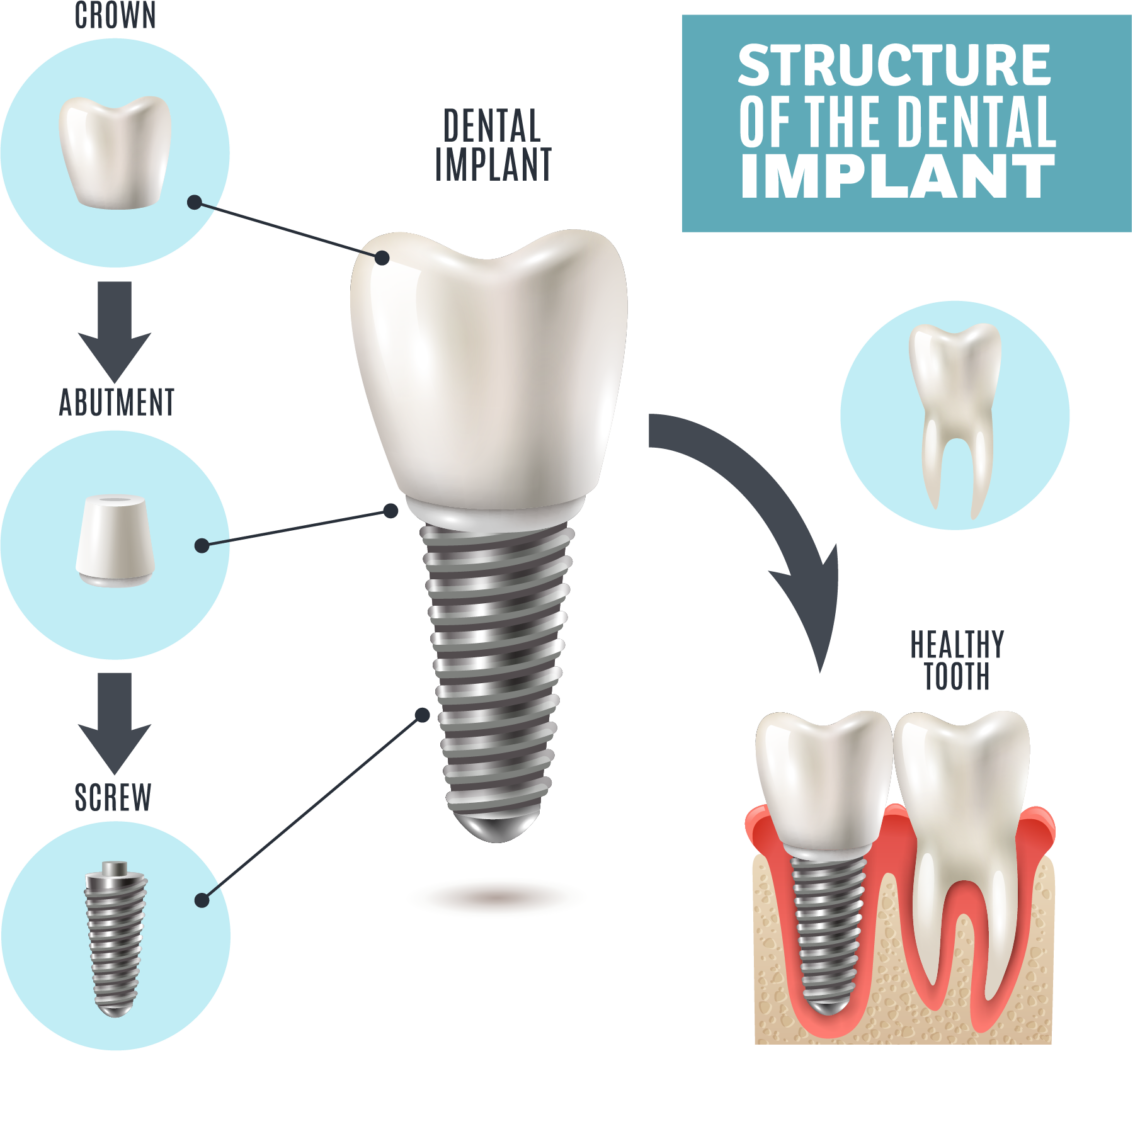

The Anatomy of The Dental Implant | Knoxville TN Dentist

What is a Dental Implant? | DDi

Dental Implant, Single Tooth

How dental implants work – Dental News Network

How do dental implants work? ⋆ Dental House

Dental Implants Portland OR | What Are Dental Implants